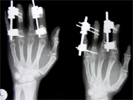

Digit lengthening in a 23 years old industrial worker

Traumatic Amputation of middle three fingers left hand at level of middle phalanx with terminilisation done

Post

Lengthening proximal phalanx of middlefinger done using unilteral fixator at stages